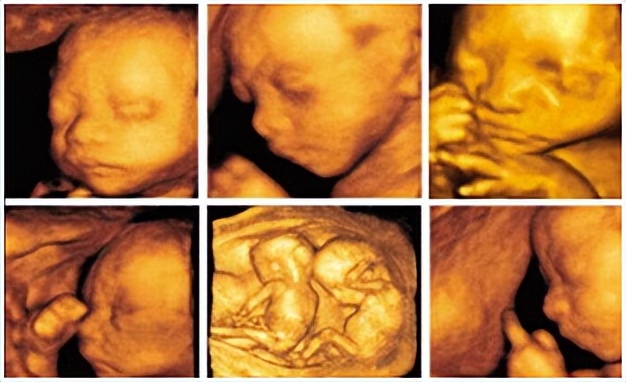

在经过了早期产检后,中孕期的妈妈们又迎来了一次大考验。这就是传说中的“大排畸”检查了。

此时胎儿在子宫内活动的空间相对较大,羊水合适,超声可以通过多个观察角度对胎儿头颈部、颜面部、胸腹部及四肢长骨、附属物等进行系统、细致的检查。

耗时较长,重点筛查胎儿的严重畸形,比如无脑儿、严重脑膨出、严重开发性脊椎裂、严重胸腹壁缺损伴内脏外翻、单腔心、致死性软骨发育不良等情况。

温馨提示:这次检查要看很多内容,检查时间相对较长,而且受孕妇腹壁脂肪、羊水、胎儿位置的干扰,图像质量会有差异,如果胎位不好时需要孕妈妈们适量活动后,待胎位变化时再行检查。